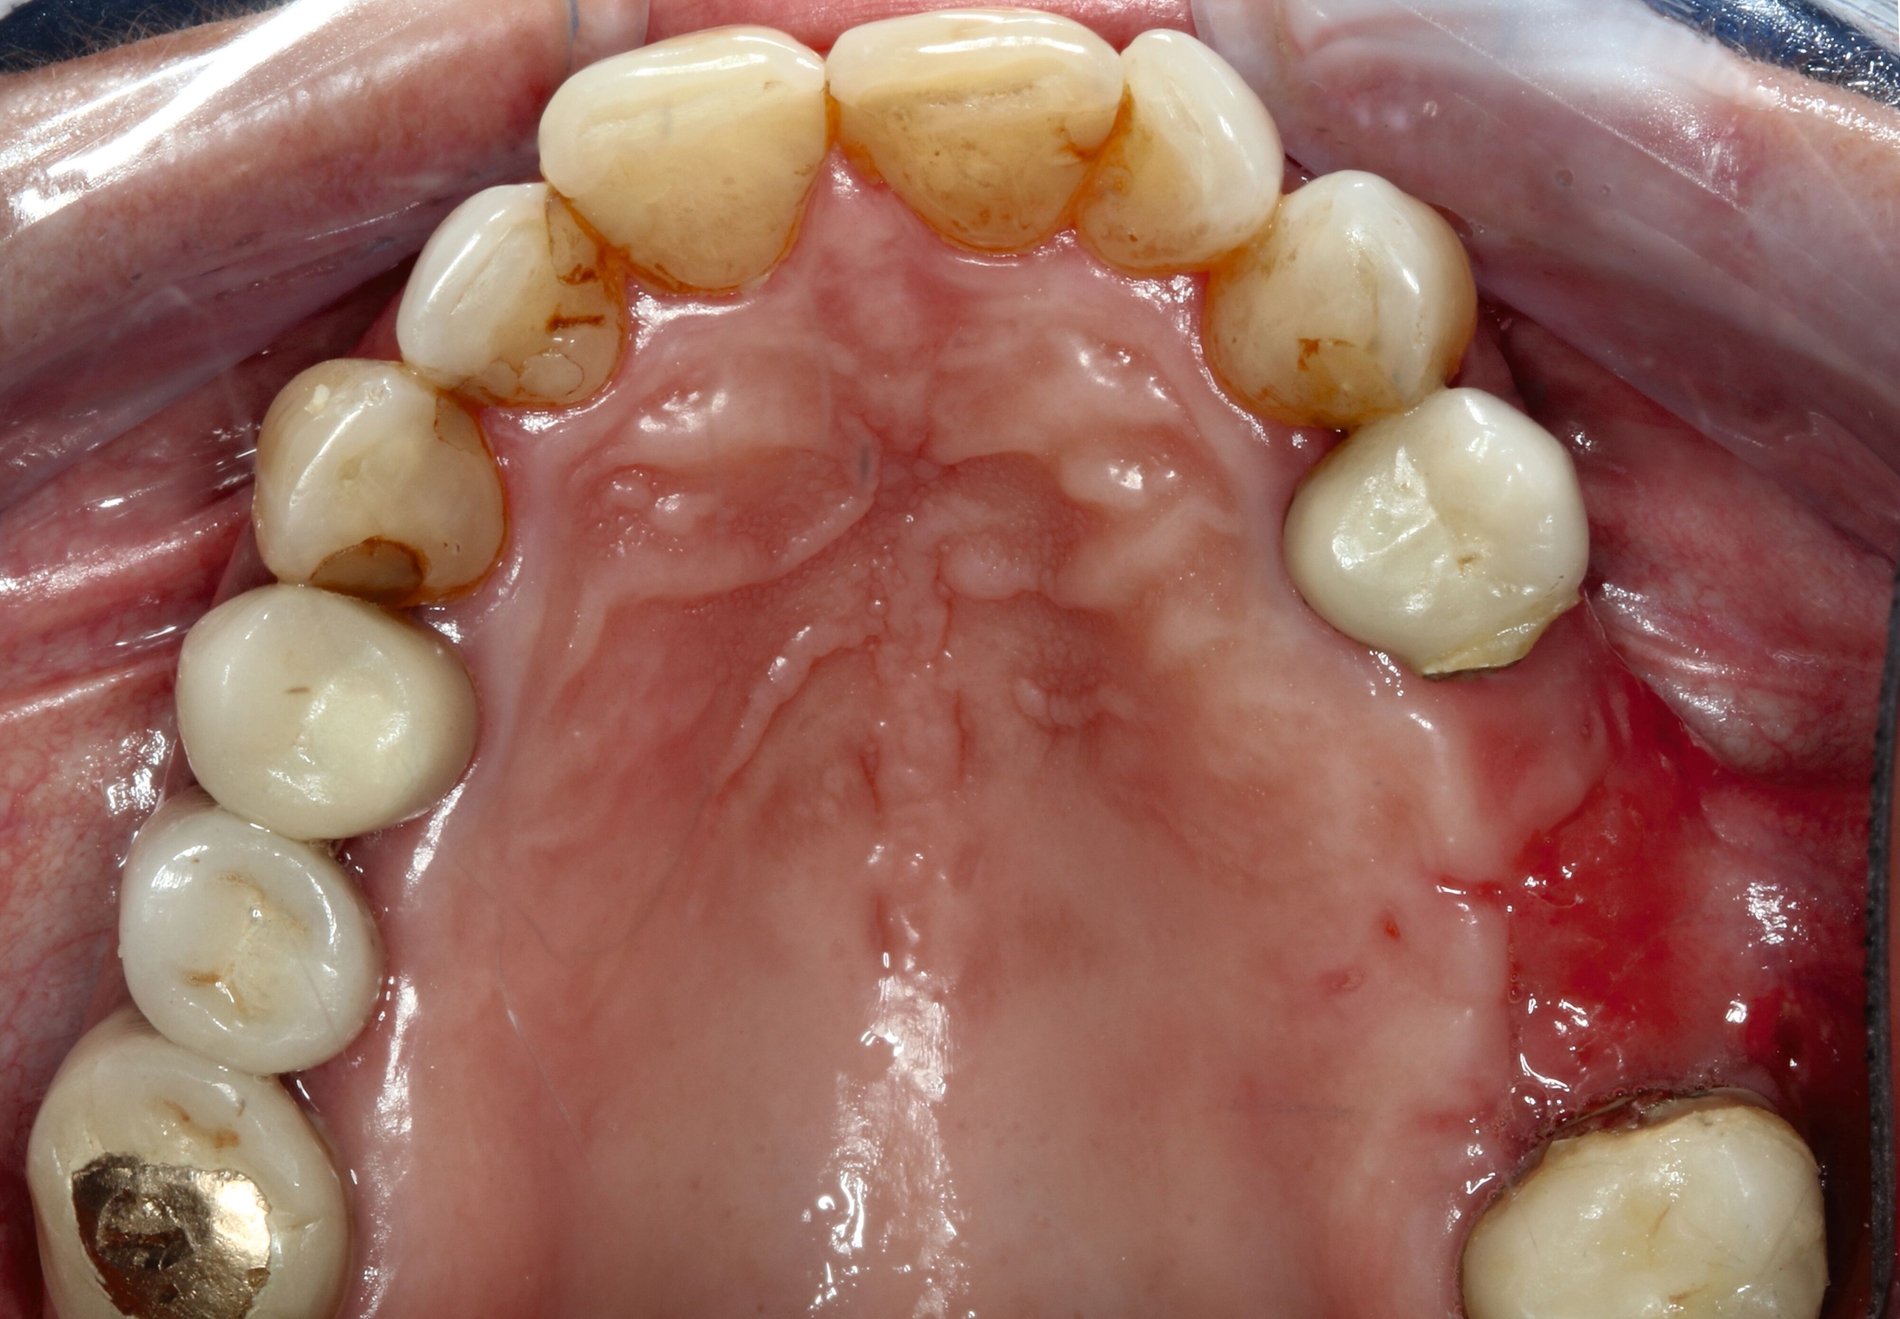

Hier wurde, neben einer klinischen Untersuchung, eine radiologische Diagnostik mittels OPG und DVT durchgeführt (Abbildung 3). Im Ergebnis manifestierte sich der dringende Verdacht, dass die überpresste Wurzelfüllung (Guttapercha-Stift/Sealer) die chronifizierte Pilzinfektion ausgelöst und unterhalten hatte. Daher wurde entschieden, den Zahn 26 zu extrahieren und gleichzeitig das überpresste Wurzelfüllmaterial zu entfernen.

Im weiteren Verlauf wurde die Kieferhöhle durch die Easy-flow-Drainage mehrmals gespült, bis sich klares Sekret über die Nase entleerte. Eine endoskopische Untersuchung der Nase zeigte keine Anzeichen für Pilzreste (Abbildung 4). Unter diesen Umständen konnte der plastische Verschluss der Mund-Antrum-Fistel durch eine Rehrmann-Plastik erfolgen. Die weiteren Kontrollen zeigten einen regelhaften Verlauf der Wundheilung, so dass der Patientin empfohlen werden konnte, eine prothetische Versorgung im zweiten Quadranten durchführen zu lassen.